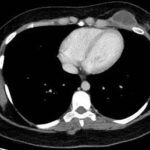

Paciente femenina de 26 años de edad, sin antecedentes patológicos de relevancia, sin dosis de vacuna BCG. Cursa con cuadro clínico de ocho meses de evolución, caracterizado por dolor en región pectoral izquierda intermitente, que se exacerba a la inspiración profunda. En el último mes se palpa masa indurada dolorosa a la palpación a nivel del cuadrante inferior interno de mama izquierda, motivo por el cual se realiza ecografía de partes blandas, donde se observa a nivel retropectoral en íntimo contacto con la parrilla costal imagen hipoecogénica de bordes delimitados, avascular al Doppler color por lo cual se solicita TC de tórax con EV. En ella se observa en topografía del cuarto espacio intercostal, imagen hipodensa con realce periférico tras la administración del contraste que desplaza por efecto de masa el parénquima pulmonar adyacente y se proyecta a la pared torácica anterolateral izquierda; mide 40 mm x 55 mm. Además, se visualiza otra imagen de similares características de base pleural en contacto con el octavo arco costal posterior izquierdo que mide 6 mm x 11 mm.

Cuatro meses posteriores a la PAAF la paciente refiere persistencia de dolor y aumento de tamaño de la masa asociado a eritema en región mamaria, por lo cual se realiza TC de tórax con contraste EV donde se observa imagen hipodensa ya conocida, con realce periférico tras la administración de contraste, con aumento de tamaño y bordes lobulados.

Hallazgos imagenológicos

Los estudios de imagen, especialmente la radiografía de tórax y la tomografía computarizada (TC), tienen un papel importante en el diagnóstico de la tuberculosis pleural, ya que la radiografía de tórax nos permite identificar el derrame pleural, la afectación unilateral y posibles consolidaciones pulmonares. En fases avanzadas, también puede mostrar engrosamiento pleural o secuelas fibrosas.

La tomografía computarizada proporciona información más detallada sobre el compromiso extrapulmonar, revelando ganglios linfáticos mediastinales aumentados o nódulos subpleurales que sugieren focos de infección activa.